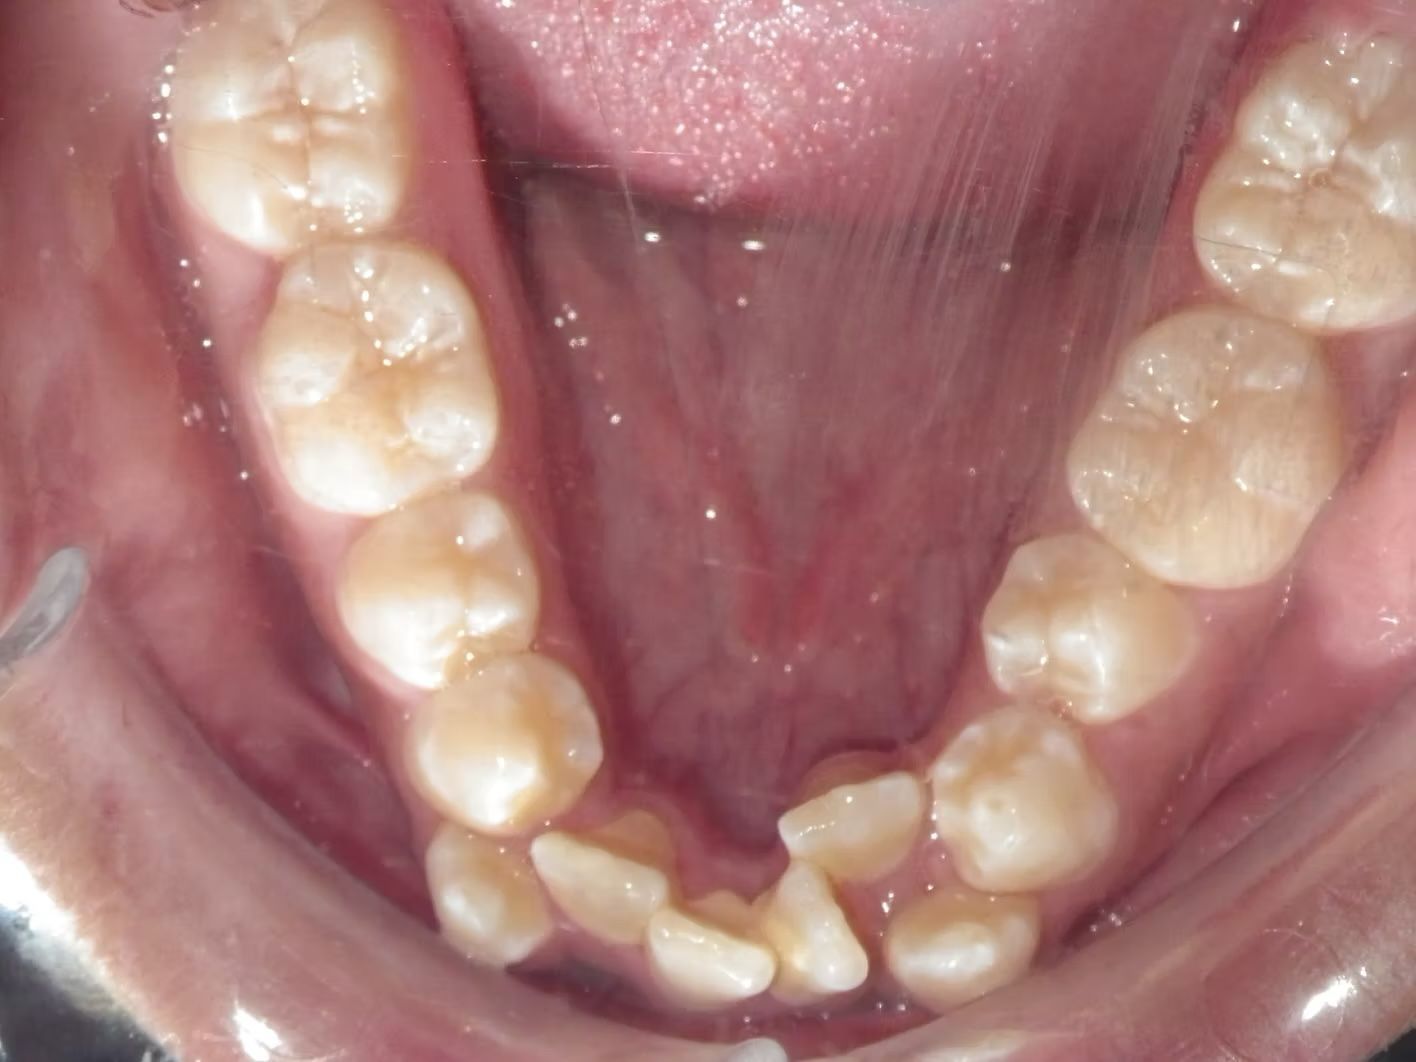

Johntavious

Johntavious didn't like that one of his lower teeth was set behind the rest. He went to many orthodontists who told him to extract the tooth or multiple teeth to correct the alignment. Johntavious and his parents didn't want to go that route and wanted to try to align the teeth without the extraction. Dr. Bret was able to successfully straighten the upper and lower teeth - fit the tooth that was back into the dental arch and make Johntavious and his parents really happy.